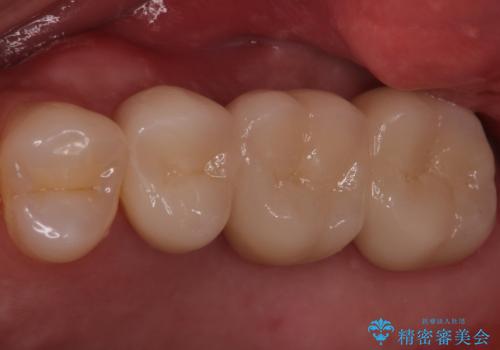

ブリッジでの修復は、抜歯後に歯がなくて噛みにくい期間が一切ありません。

歯茎の状態も良く、適合の良いブリッジを装着することができました。